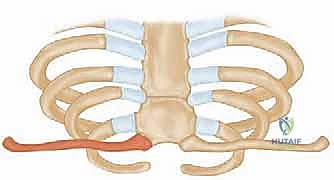

The epidemiological distribution of these injuries heavily favors anterior dislocations, with contemporary series reporting anterior-to-posterior dislocation ratios ranging from 3:1 to as high as 20:1. The mechanism of injury dictates the direction of displacement. Anterior dislocations typically result from an indirect force—specifically, a lateral compressive force applied to the shoulder girdle while the shoulder is rolled backward in extension. Conversely, posterior dislocations result either from a direct, high-energy blow to the anteromedial clavicle, or an indirect lateral compressive force applied while the shoulder is rolled forward in flexion. While anterior dislocations present a prominent, often cosmetically displeasing deformity, they are rarely life-threatening and can frequently be managed with non-operative, symptomatic care.

Acute posterior dislocations, conversely, demand immediate attention. Closed reduction should be attempted urgently, ideally within the first 48 hours, in a controlled environment such as the operating room with general anesthesia and cardiothoracic surgery available on immediate standby. The classic reduction maneuver involves placing a bump between the patient's scapulae, applying lateral traction to the abducted and extended arm, and utilizing a sterile towel clip to physically grasp the medial clavicle and lift it anteriorly. If closed reduction is successful, the joint is often stable, and non-operative management in a figure-of-eight harness or sling is appropriate. Operative intervention is strictly indicated when an acute posterior dislocation is irreducible by closed means, when it is highly unstable post-reduction, or when there are progressive signs of mediastinal compression (vascular compromise, dyspnea, dysphagia) that do not resolve with reduction attempts.

Patient positioning in the operating room requires meticulous attention to detail. The patient is placed in the supine position on a radiolucent operating table. A rolled towel or a specifically designed gel bump is placed vertically between the scapulae. This maneuver allows the shoulders to fall posteriorly, effectively opening up the anterior chest wall, retracting the lateral clavicle, and facilitating reduction of a posterior dislocation. The head is placed on a Mayfield horseshoe headrest or a standard foam donut, and the neck is slightly extended and rotated away from the operative side to maximize exposure of the sternocleidomastoid and the medial clavicular region.